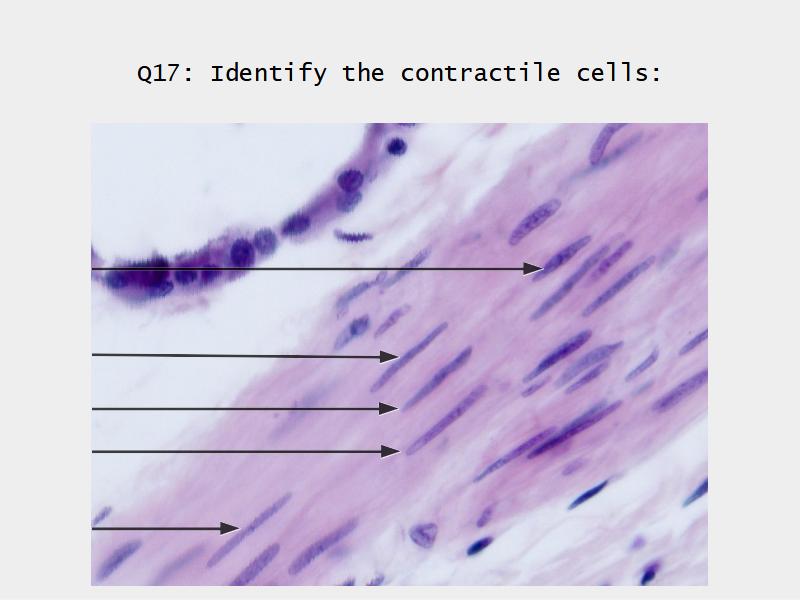

Name three types of contractile cells.